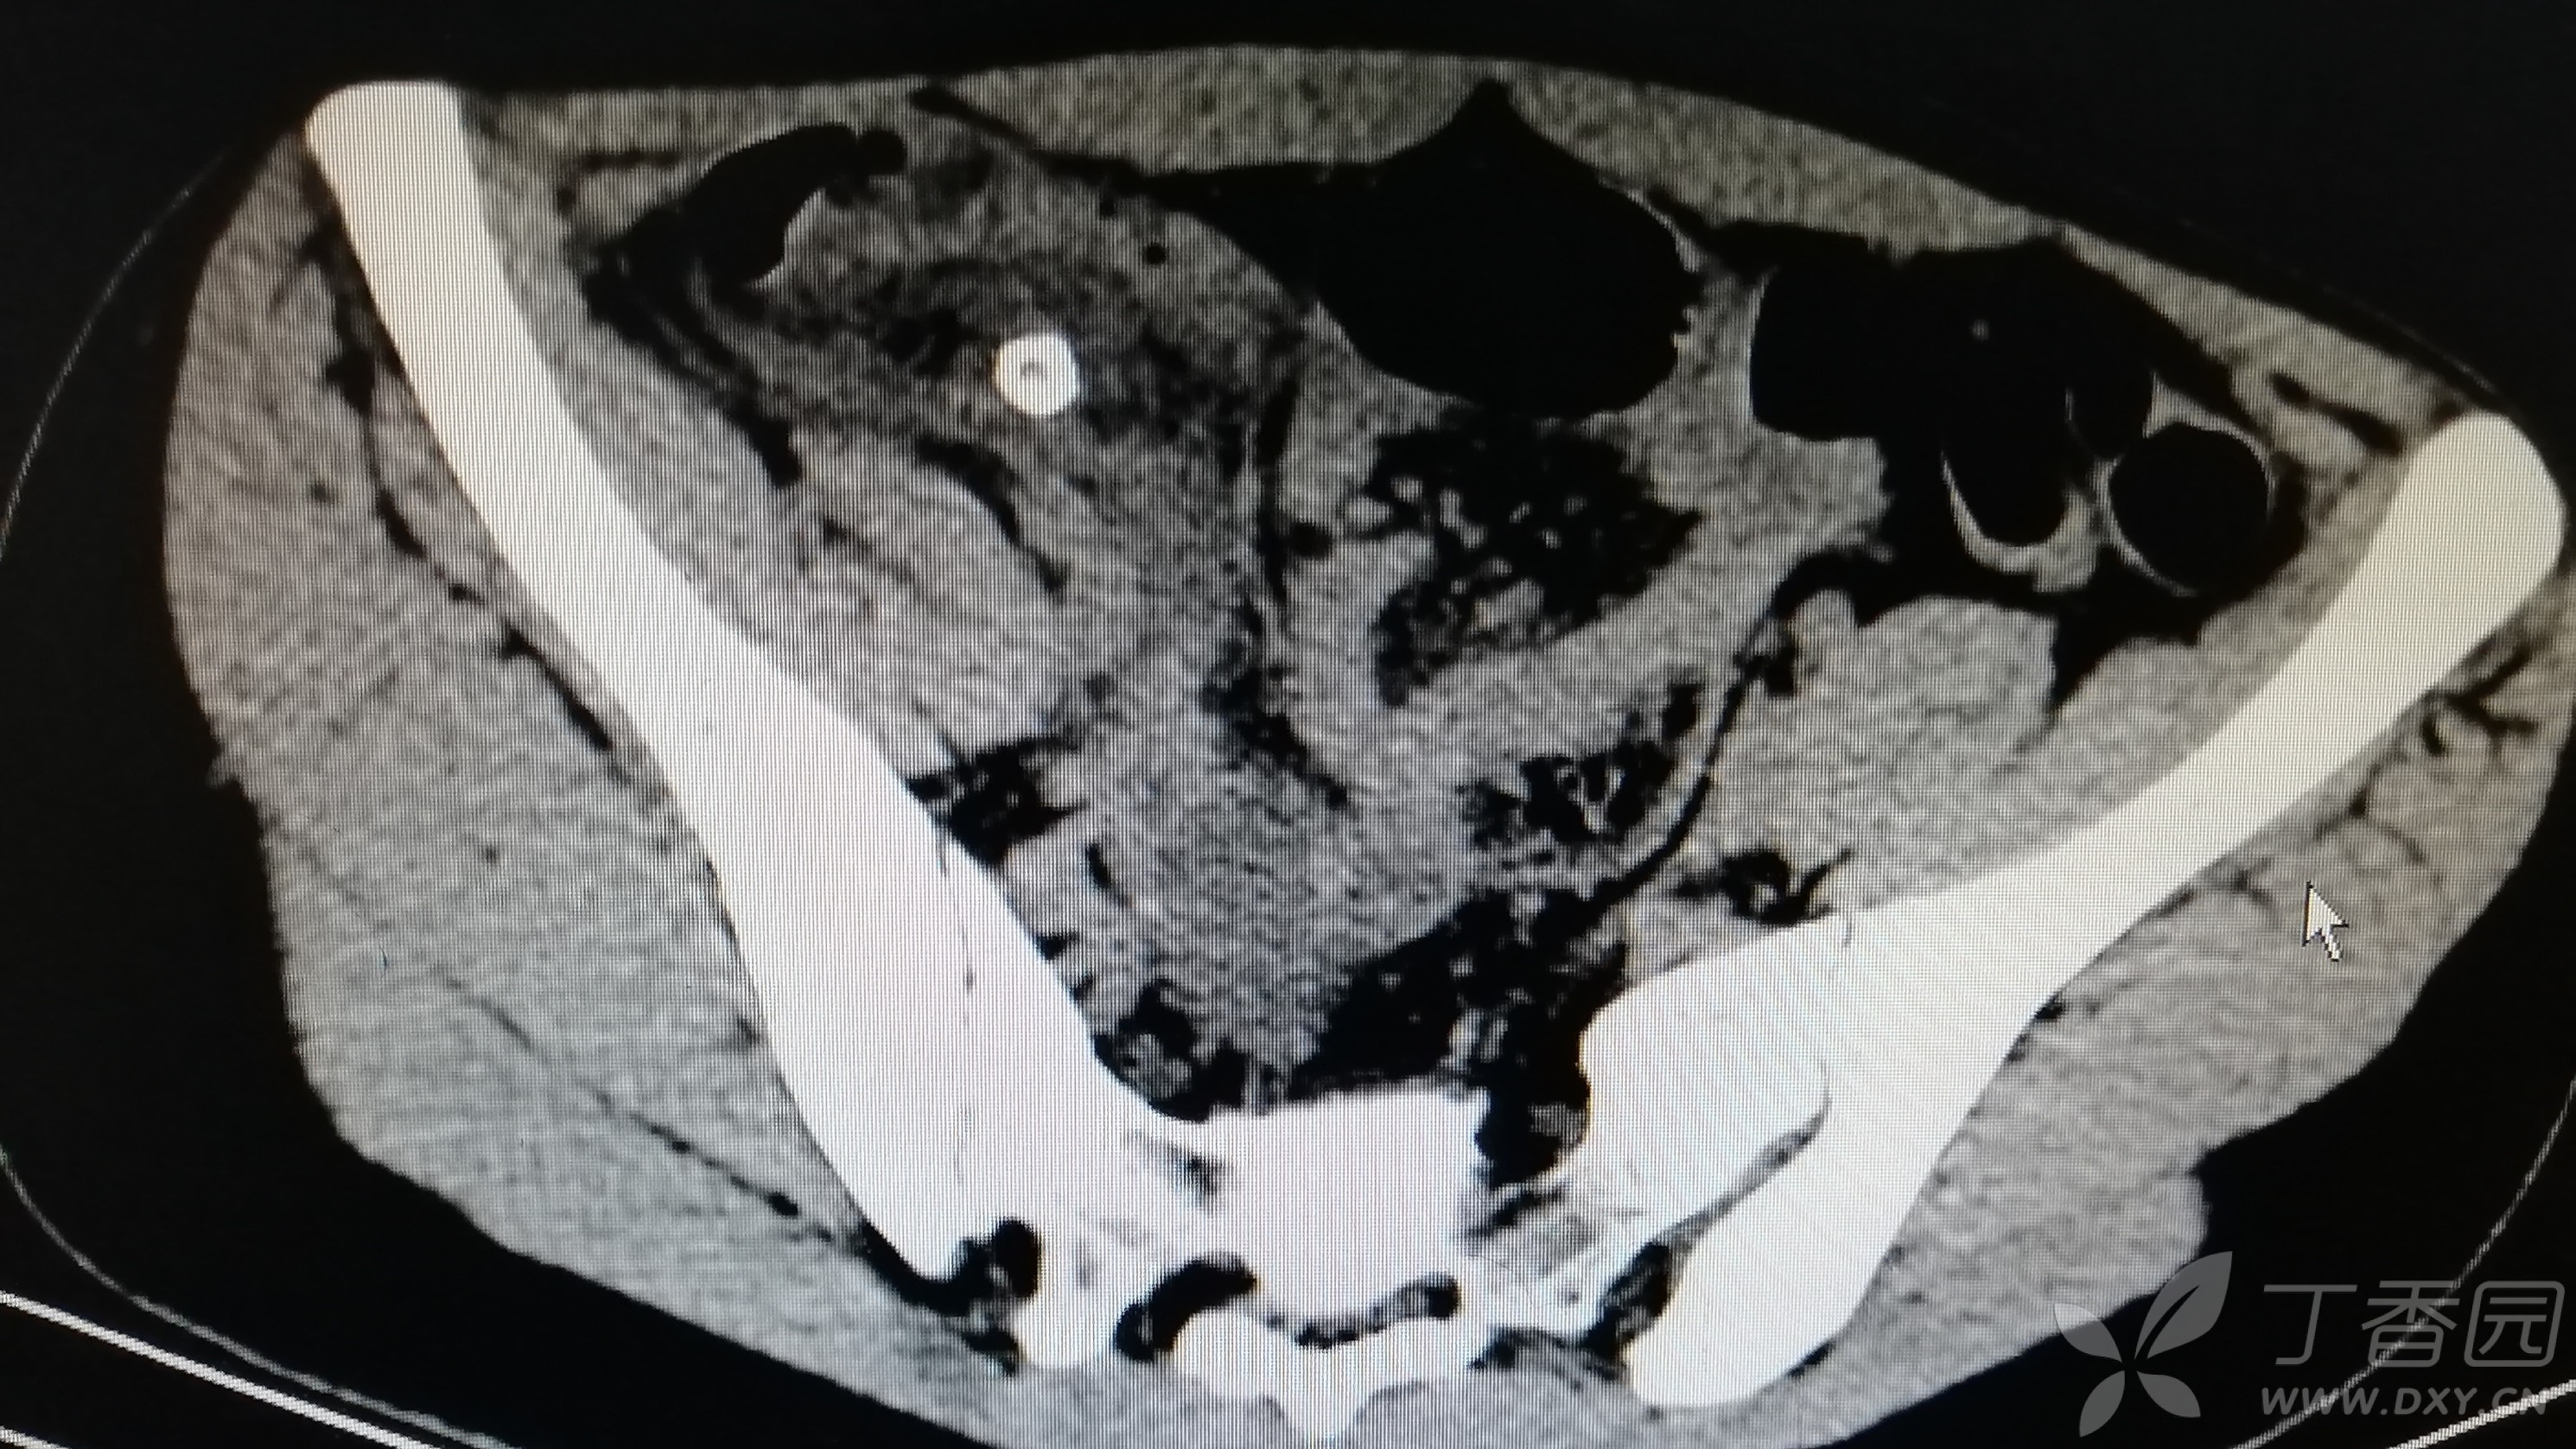

行ct检查发现阑尾增粗,腔内有粪石,见以下图示.

图片尺寸512x512